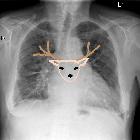

Stag's antler sign (lungs)

antler sign (lungs) • Cephalisation of pulmonary veins in congestive cardiac failure - Ganzer Fall bei Radiopaedia

antler sign (lungs) • Cardiogenic pulmonary edema grade 1 - Ganzer Fall bei Radiopaedia

nicht verwechseln mit: Antler sign (lung)The stag's antler sign, also known as the hands-up or inverted moustache sign, refers to upper lobe pulmonary venous diversion in pulmonary venous hypertension or pulmonary edema as seen on an erect frontal chest radiograph.

The prominence of upper lobe pulmonary veins resembles a stag's antlers. It is the earliest sign of pulmonary venous hypertension (grade 1 pulmonary edema).